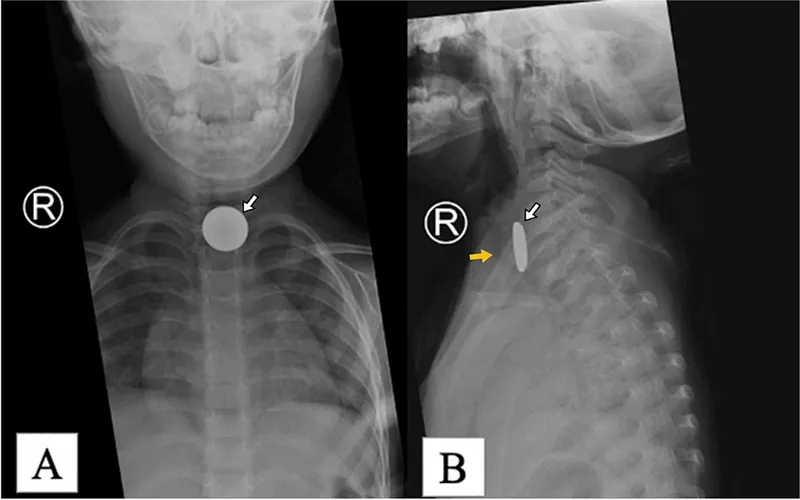

- X-ray (AP/Lat): First-line. Shows radio-opaque FBs.

- 📌 Coin Sign: Esophagus (AP: O, Lat: |), Trachea (AP: |, Lat: O).

⭐ A coin in the esophagus typically appears as a circle (en face) on an AP X-ray, while in the trachea it appears as a circle on a lateral X-ray (sagittal orientation).

- ⚠️ Esophageal: Remove <2 hrs. X-ray: Halo (AP), step-off (Lat).

- Esophageal coins: Appear circular on AP X-ray. Tracheal coins are edge-on.